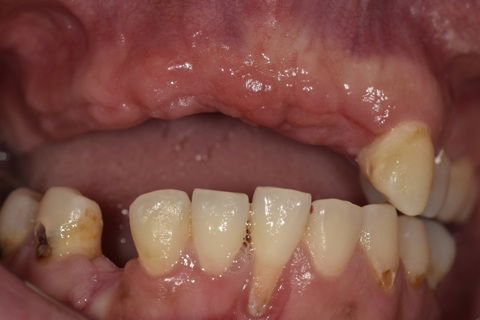

Visão Frontal Pré-Cirúrgica

As características ideais dos tecidos que virão a receber uma prótese são: (1)Ausência de patologias; (2) Espessura e altura do rebordo adequadas; (3) Ausência de espículas Ósseas; (4) Ausência de hiperplasias de tecido mole.